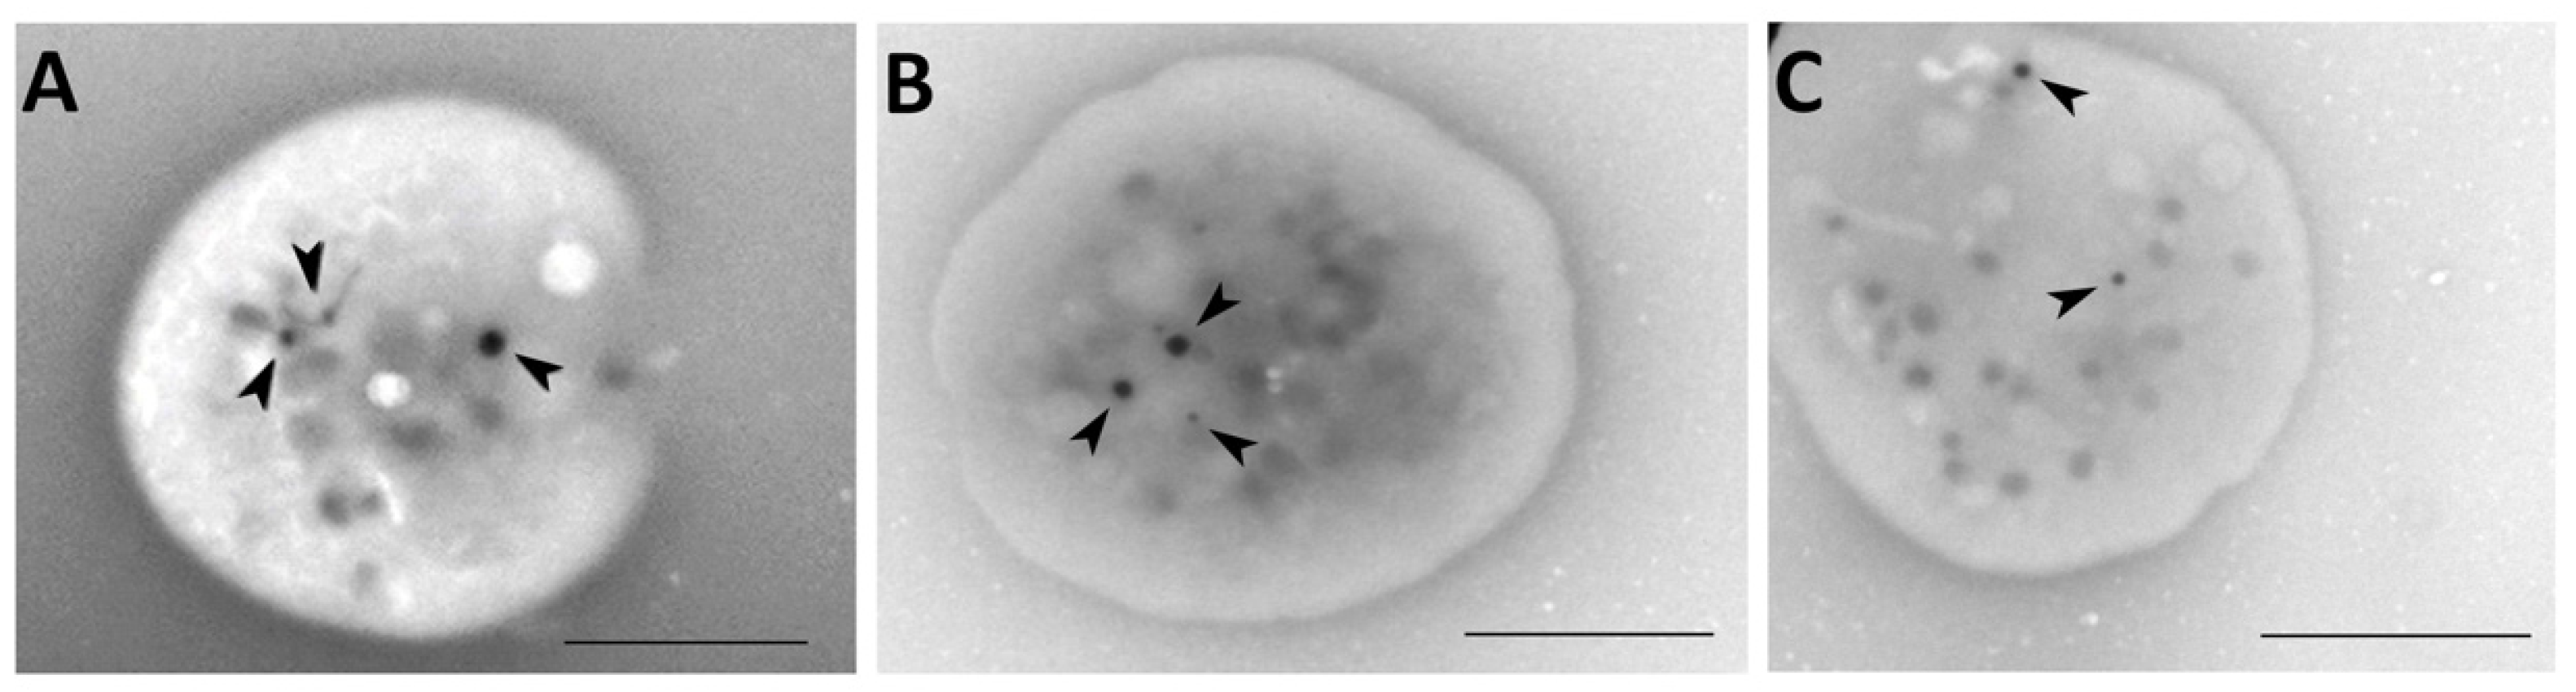

2.7. Whole Mount Transmission Electron Microscopy

3.3. Transmission Electron Microscopy

4.7. Whole-Mount Transmission Electron Microscopy